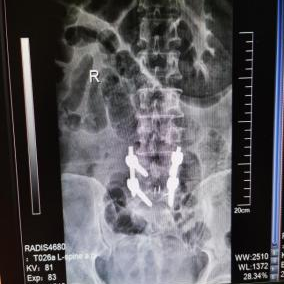

12月17日,贵州航天医院第88次晨读会由我院骨一科主任、副主任医师陈明勇作学术交流,他以“肱骨近端骨折并肩关节脱位的手术治疗”为题,全面讲解了该损伤的手术策略、术中血供保护理念及内侧支撑重建技术等内容,并通过多个典型病例图文资料分享了从损伤机制分析、手术步骤实施到术后随访评估的完整过程与关键细节,为临床处理此类复杂骨折提供了较为全面的技术参考,有助于在手术规划中结合个体情况开展针对性治疗。 贵州航天医院 骨科专家简介 陈明勇 骨一科主任,副主任医师 临床擅长:从事创伤骨科工作约20年,对骨缺损、骨不连、骨肿瘤、肢体畸形等的肢体矫形重建及功能重建,慢性化脓性骨髓炎的根治治疗、糖尿病足的保肢治疗、快速康复理念(ERAS)下的老年骨折的诊治,四肢复杂骨折的诊治,四肢骨折等微创手术治疗具有丰富的临床经验。 2004年毕业于遵义医学院临床专业,曾在中国人民解放军总医院、广西医科大学第一附属医院、上海第六人民医院骨科进修。中国中西医结合学会骨伤科专业委员会横向骨搬移治疗糖尿病足及微血管网再生学组首届委员,遵义市医学会创伤分会常务委员。 瞿 晖 骨科党支部书记,骨二科主任,副主任医师 临床擅长:对骨科的常见病、关节外科、脊柱外科及运动医学疾病的诊治具有丰富的临床经验,熟练掌握骨科手术操作技术。 毕业于遵义医学院临床医学系,2005年前往广州中山大学第一附院骨显微医学部进修学习,2011年前往成都华西医院进修学习,并多次在省内外学习骨科相关知识,是中华医学会骨科分会会员。 赵小锋 中共党员,骨二科副主任,副主任医师 临床擅长:从事骨科临床工作11年,对骨科常见病、多发病诊疗有较为丰富的临床经验,擅长脊柱相关疾病诊断及治疗,尤其是颈、腰、腿疼痛疾病诊断及治疗,擅长胸腰椎骨折微创经皮穿刺内固定术、经皮穿刺椎体成形术、经皮穿刺脊柱内镜下腰椎间盘摘除术、单纯开创腰椎间盘摘除术、腰椎滑脱复位椎间植骨椎融合内固定术、腰椎管狭窄减压融合内固定术及人工髋、膝关节置换术等。 2012年毕业于遵义医学院外科学专业硕士研究生,2019年参加“遵义市115医学人才精英计划”于上海交通大学第一附属医院培训学习,2023年于北京大学第三人民医院脊柱外科进修学习,曾获得遵义市优秀医师荣誉称号。 遵义市手外科第一届委员,遵义市医学会创伤分会第一届委员,遵义市医学会创伤分会第二届委员,贵州省康复医学会第三届脊柱脊髓专业会委员,遵义市医学会烧伤与整形外科学分会委员,发表论文5篇,其中国家级核心期刊1篇,SCI论文1篇,主持市级课题1项并结题,参与市级课题2项。 赵兴东 骨科主任医师 临床擅长:擅长骨科的常见病及各种创伤、四肢骨折创伤修复、骨感染、手足疾病的诊治和手足体表畸形的矫形整复,熟练掌握骨科四肢骨病及创伤的手术操作技术,尤其在四肢关节复杂性损伤、手足外伤、组织缺损创面、难治创面的皮瓣修复方面及平足、高弓足矫形方面及四肢慢性疼痛诊治、康复方面具有丰富的临床经验。 硕士研究生,毕业于遵义医学院临床外科系,2015年前往山东省立医院手足外科进修学习;遵义市医学分会创伤分会第一、二届委员,遵义市手外科医学会第二委届员会常务委员;在省级及省级以上期刊发表文章9篇,参编著作2部,参与主持并完成市级课题1项,参与市级课题2项、省级课题1项。 张艳金 中共党员,骨科副主任医师 临床擅长:从事骨外科工作16年,对复合伤、多发伤的救治、四肢骨干骨折、关节周围骨折、骨肿瘤、骨髓炎等诊治具有丰富的临床经验。 中共党员,硕士研究生,2006年本科毕业于山西医科大学第二临床医学院,2011年研究生毕业于北京军区总医院;在“老年COPD患者合并髋部骨折的诊治”国际合作课题组研究两年,在老年髋部骨折的诊治方面具有丰富的经验,并发表论文6篇;主持遵义市级课题1项,承担遵义医科大学的临床教学工作,获得遵义医科大学优秀带教老师荣誉。编撰有《骨科疾病诊疗精粹》一书,开展2项新技术,编撰地方规范《务川自治县创伤骨科常见疾病诊疗规范》一书。 张俊凯 骨科副主任医师 临床擅长:从事骨科临床工作28年,对创伤骨折、骨感染、骨缺损、骨不连等外科诊治,四肢骨折的微创手术治疗,四肢复杂骨折(如关节内粉碎性骨折、多发骨折等)的损伤控制及手术治疗等具有丰富的临床经验。 1995年毕业于遵义医学院临床专业,2009年前往复旦大学附属医院骨科进修1年。 卢懿明 中共党员,骨科副主任医师 临床擅长:从事骨科工作18年,对创伤骨折、四肢骨折的微创手术治疗、四肢复杂骨折(如关节内粉碎性骨折、多发骨折等)的损伤控制及手术治疗,尤其是髋部骨折的PFNA等微创技术,踝关节骨折、膝关节周围骨折的Mipo微创技术等具有丰富的临床经验,开展了4项新技术,发明6项新型专利技术。 2005年毕业于遵义医学院临床专业,2017年,前往南方医科大学第三附属医院骨科进修半年,回院后运用Mipo技术对骨干骨折及干骺端骨折的治疗技术,同时积极开展骨盆骨折、髋臼骨折腹直肌外侧切口的应用;发表了多篇专业论文,经常参与省内外学术交流会授课,获得医院荣誉称号多个。 邬夏荣 骨科副主任医师 临床擅长:从事骨科工作16年,对四肢复杂骨折、骨肿瘤的诊治,尤其是足踝创伤、慢性踝关节损伤、平足症等诊疗具有丰富的临床经验。 2006年毕业于遵义医科大学临床医学专业,曾在陆军军医大学西南医院进修学习,发表多篇骨科学术论文。 余德怀 中共党员,骨科副主任医师 临床擅长:从事骨科工作10余年,对运动医学、骨关节、脊柱外科常见病、多发病的诊治具有丰富的临床经验。 硕士研究生,2011年毕业于遵义医学院临床医学专业,曾前往遵义医科大学附属医院运动医学专业进修学习;是贵州省医学会运动医学分会青年委员,西部关节镜联盟委员;发表多篇骨科学术论文。 冯 乾 骨科副主任医师 临床擅长:从事骨科工作近20年,熟练掌握骨科多发病及常见病的诊治,尤其对脊柱退变性疾病的诊断及治疗具有丰富的临床经验,主要研究脊柱微创相关治疗方式,能熟练开展椎间孔镜及UBE。 曾前往北京大学第三医院进修学习疼痛及椎间孔镜、首都医科大学友谊医院专业进修脊柱内镜;是贵州省康复医学会第三届脊柱脊髓专业委员会委员;发明专利3项、发表脊柱外科专业论文多篇。 贵州航天医院骨科简介 基本情况 贵州航天医院(原3417医院)骨科组建于1968年,前身是以创伤和断肢(断指)再植闻名于世的上海市第六人民医院骨科,中国断肢(断指)再植的奠基者、中科院院士陈仲伟等专家莅临科室指导医疗和教学,并在70年代开展了贵州省首例断肢(断指)再植手术。组建50余年来,诊治患者已逾百万,挽救了无数的伤病员,成为了保障遵义地区人民群众健康的重要支撑。 经过几代人的不懈努力,今天的骨科,已由创伤骨科发展至骨病、骨肿瘤、骨结核等领域,现有脊柱外科、关节外科、四肢创伤、手足外科四个亚专科,成为了集医疗、教学、科研于一体的综合学科,是贵州省临床重点专科、遵义市临床重点专科、遵义市骨科临床医学中心、遵义市基层骨科专科联盟理事长单位。 科室目前开放床位110张,共有医护人员50余人,副高级以上专家18人,硕士研究生15人。拥有一流骨科医疗设备多台,每年不定期选派优秀技术骨干到全国各大知名医学院校进修、学习、参观、交流,并邀请国内、国外知名专家教授来院进行交流、指导,通过不断引进国内外先进的诊疗技术,科室医疗技术水平稳步提升,为广大人民群众提供了优质的医疗服务。 专科特色 骨一科 (一)骨缺损、骨不连的肢体与功能重建 胫骨横向骨搬移技术治疗糖尿病足: (二)慢性骨髓炎的根治治疗 (三)肢体缺血性疾病如糖尿病足、脉管炎的保肢治疗 (四)皮瓣修复 (五)复杂创伤的治疗 (六)老年髋部骨折及小儿骨折快速手术 老年髋部骨折: 骨二科 (一)胸腰椎骨折微创经皮椎弓根螺钉固定术 (二)老年性骨质疏松性患者腰椎滑脱脊柱内固定术(骨水泥螺钉) (三)V形双通道脊柱内镜技术(VBE)腰椎融合术治疗腰椎退行性疾病 (四)老年性骨质疏松性骨折(PVP/PKP)术 (五)人工髋关节置换术 (六)双侧股骨头坏死人工全髋关节置换 (七)右侧全髋置换术后假体周围骨折翻修 (八)人工膝关节置换术 (九)人工膝关节假体松动翻修 (十)关节镜技术 传统手术切口 关节镜技术切口 诊疗范围 骨一科 1.四肢创伤、矫形。 2.手、足踝外科。 骨二科 end